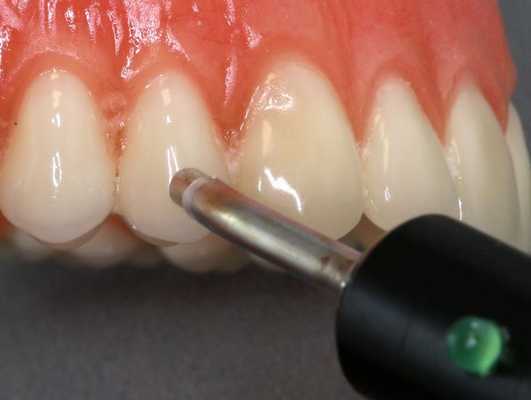

В случае наличия кариозной полости зондирование ее стенок и дна при периапикальном абсцессе безболезненно. При вскрытой пульповой камере в корневых каналах определяют путридные массы или пломбировочный материал. При хроническом течении заболевания на слизистой обнаруживают свищевой ход. Симптом Лукомского положительный. Пульповая камера имеет соединение с кариозной полостью. В большинстве случаев причинный зуб ранее лечен. Термопроба при периапикальном абсцессе отрицательная. ЭОД используют для определения витальности пульпы. Значение чувствительности пульпы в пределах от 2 до 20 мкА говорит о ее жизнеспособности, показатель от 20-100 мкА сигнализирует о развитии воспалительного процесса. При периапикальном абсцессе результаты ЭОД находятся на уровне от 100 мкА и выше, что свидетельствует о распаде пульпы с вовлечением в воспалительный процесс тканей периодонта.

- Электроодонтометрия. С помощью ЭОД определяется степень поражения пульпы. Для острых форм периодонтита характерны показания ЭОД в интервале 180–200 мкА, для хронических – 100–160 мкА.

ЭОМ — это метод стоматологического исследования, основанный на определении порогового возбуждения болевых и тактильных рецепторов пульпы зуба при прохождении через неё электрического тока.